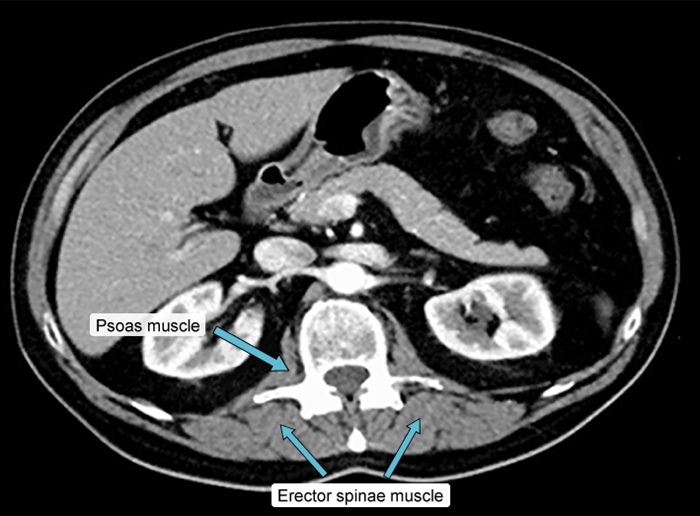

Back Muscles

The arrow points to a bilaterally symmetric structure that lies in close association to the vertebral body and vertebral transverse process. This is the psoas muscle, which originates from the anterior surface of the transverse processes and lateral surface of the vertebral bodies at T12-L5. Inferiorly (at around the level of the inferior ligament), the psoas muscle combines with the iliacus muscle(Choice B) to form the iliopsoas muscle, which functions in hip flexion. Intraabdominal or more distal infections can spread to these muscles (eg, psoas abscess) and cause abdominal pain, fever, and weight loss. HIV, intravenous drug use, and diabetes are risk factors for primary psoas abscess development.

(Choice A) The erector spinae (also shown in the image above) is a large muscle group of the back that courses longitudinally along the spinous processes. Bilateral contraction causes spine extension.